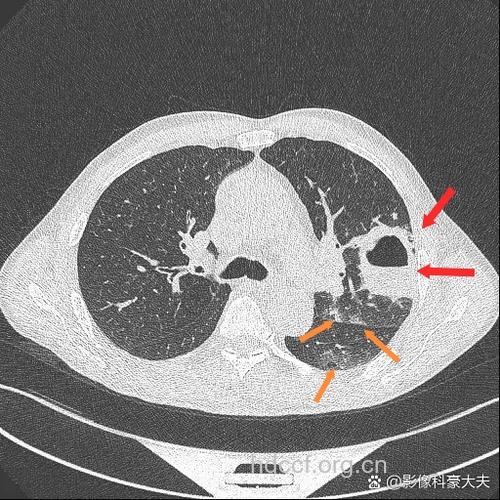

1.两肺多发片状致密阴影,边缘模糊,大小不一,外围较多。

2.两肺多发圆形或椭圆形结节状、团块状阴影,边缘较清楚,继而液化出现含液平的脓肿,间有新的病灶出现和液化。

3.上述炎症吸收后,可有局部纤维化或形成气囊。